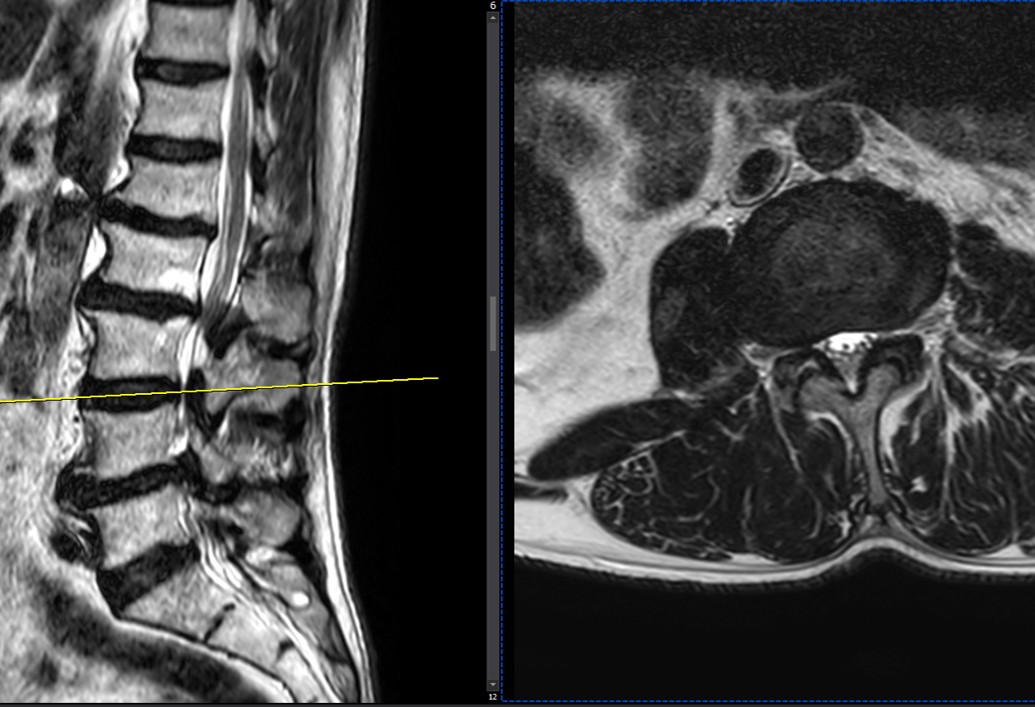

41 years old man presented to my clinic in October 2023 with acute and sever R neck pain with radicular pain to his R upper extremity along C6 dematom since 2 weeks ago. Examination didn’t show any upper motor signs. Was suggested urgent surgery

I ordered EMG/ NCV : showed mild R C6, C7 irritation without any active axonal loss

In his MRI was reported R. para R. IVF Massive extrusion. I decided to control his pain and manage this patient with reevaluation of patient every other session. For 5 sessions i just used acupuncture and laser and IFC and mild adjustments to his R. T3-T7 and mild arthosteem to above and below involved segment. Cervical adjustment considered contraindicated for this patient. From session 6th- 8th i started to use mild/gentle cervical decompression. He used soft cervical collar all the time. His pain decreased by 80 percent

I gave him cervical traction pump to be used 3-5 times per day at home for the next 3 months and i released the patient. He was evaluated every week once for one month and after that every 2 weeks. After 3 month I repeated MRI. Size of the herniated disc was reduced greater than 50 percent. Asked him to do another mri in 6 months

In general: Precise selection of the patients, examination,diagnosis, plan of management, reevaluation and treatment can be done by doctors of chiropractic for the patients with spinal disc herniation and stenosis Moreover giving reasonable time to these kind of patients under direct supervision by their chiropractic doctors can prevent unnecessary surgery. Proper selection of these kind of patients is another important fact that can be done precisely by chiropractors.

MRIs before and after proper management of this patient: